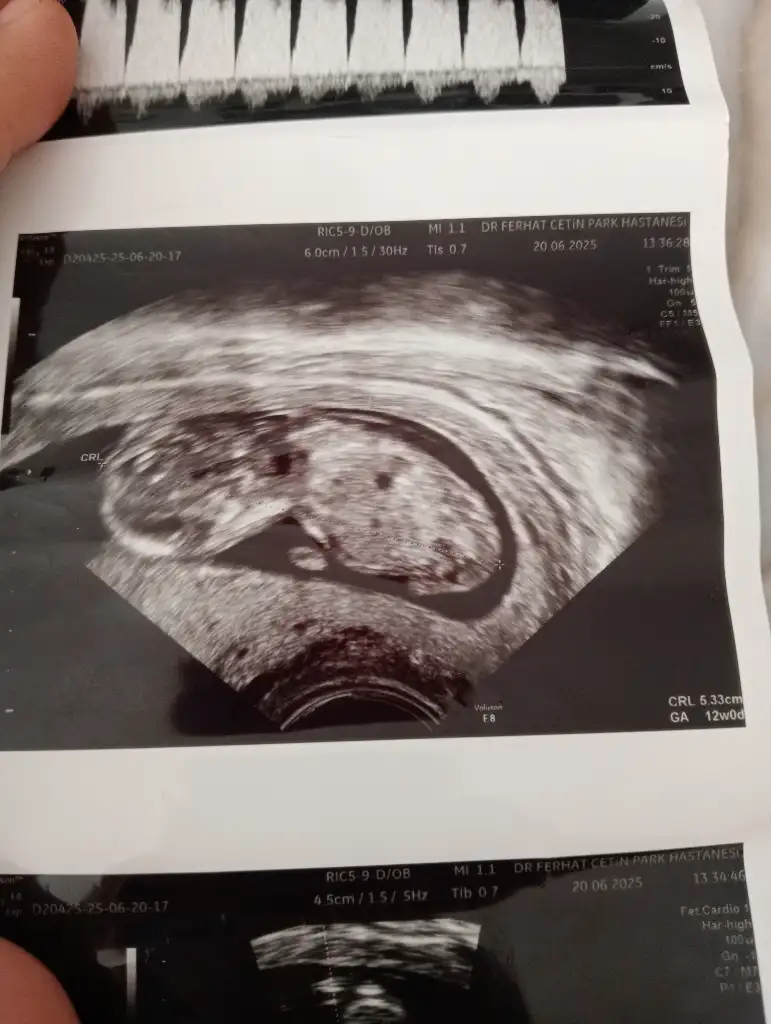

Kızlar nasılsınız 3-4 gündür bakamamıştım buraya bazı arkadaşlar ceza almış üzüldüm:( ilk çocuğumda burda yine konuşurken bizde böyle grup kuralım demiştik ceza yemiştik ama hala grubumuzla aktifiz 5 sene oldu😅 11+1 de salı günü fetal dna testi yaptırdım doktorda yine ikili tarama gibi ölçümler yaptı iyi görünüyor dedi erkeğe benzetti bakalım sağlıklı olsunda nasipte ne varsa kabulümüz😍

Kızlar cinsiyet tahmini yapabilecek var mı?😊

• 17504242968966795354498347858035.webp

17504242968966795354498347858035.webp

35,2 KB · Görüntüleme: 52